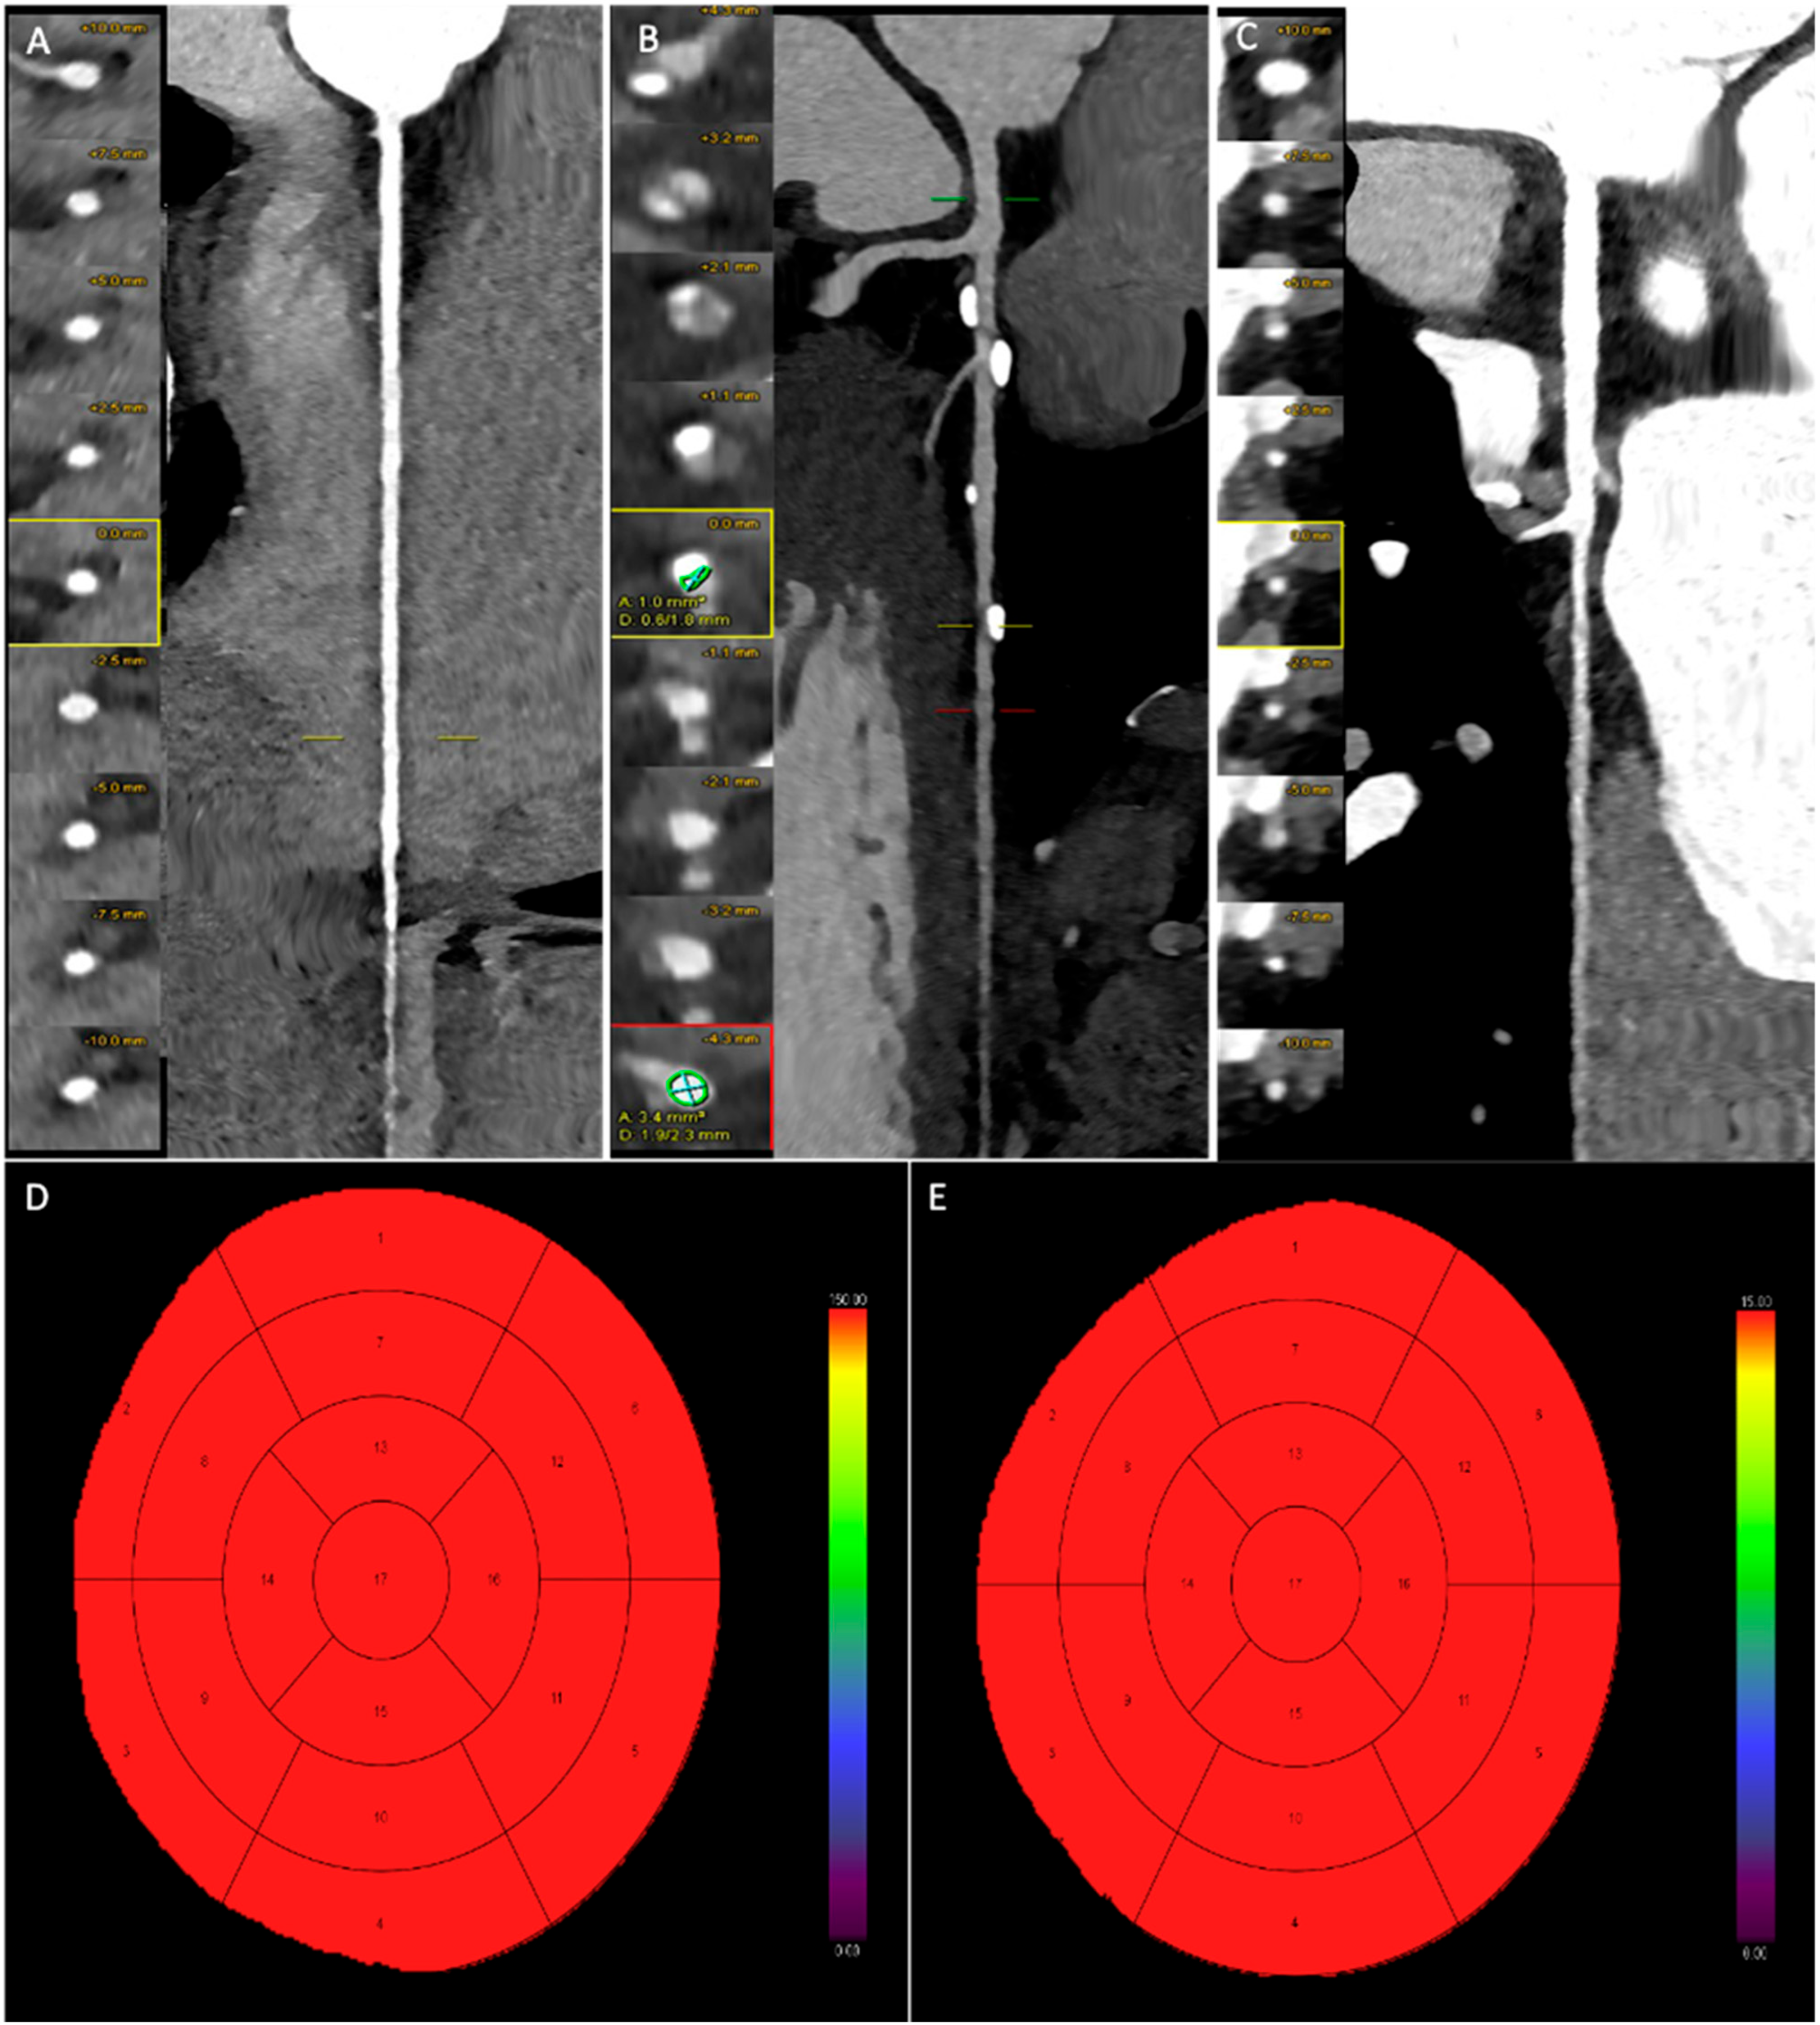

2.4. Dynamic CT-MPI Analysis

3.4. Dynamic CT-MPI Analysis